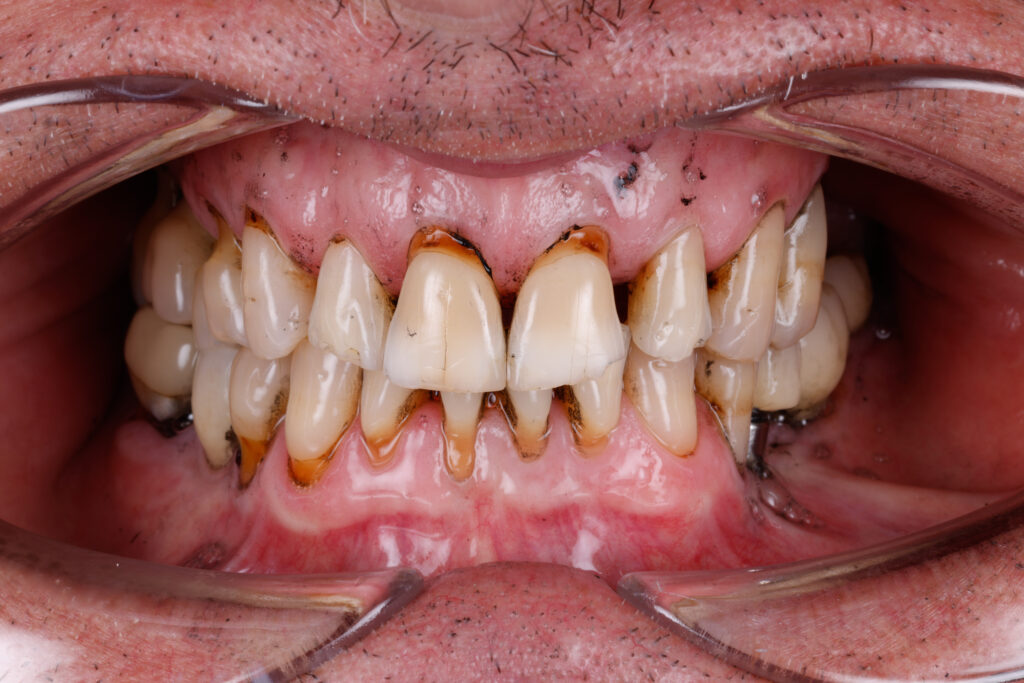

Before

After